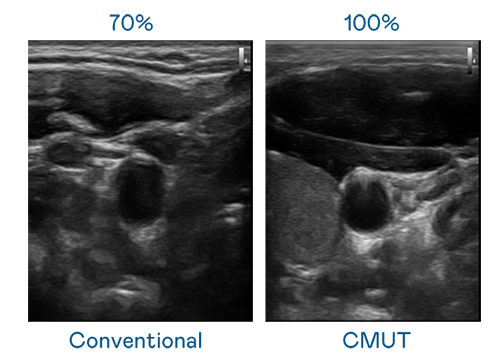

CMUT 技术是一种用电容式微机电元件来产生超音波讯号的技术。与传统 PZT 压电式技术相比,CMUT 频宽增加 30%,更宽频的超音波讯号让影像解析度大幅提升,是实现高影像品质医疗超音波扫描、促进精准医疗发展的关键技术。

大频宽带来超清晰影像

超音波影像的解析度高低,首先取决于探头能发出的讯号频宽。羞羞视频18 CMUT 可提供高清晰的超音波讯号,提供高频宽、高灵敏度、影像纹理细节更高的超音波影像,协助医护人员缩短影像判读时间及利用精准的医疗影像进行诊断。